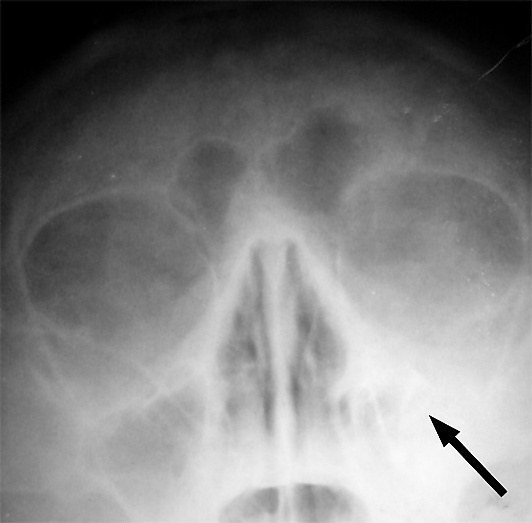

Одним из основных симптомов гайморита является тянущая боль, которая возникает при наклоне туловища вперёд. Подтверждение диагноза производится на основании рентгеновского снимка.

Диагностика синуситов

Диагноз ставится на основании данных анамнеза, клинического обследования и результатов дополнительных методов исследования, в частности, рентгенографии, целью которой является выявление затемнений в поражённых пазухах носа или компьютерной томографии придаточных пазух носа, а также риноскопии, в процессе которой выявляются изменения в слизистой полости носа и полипы[18].